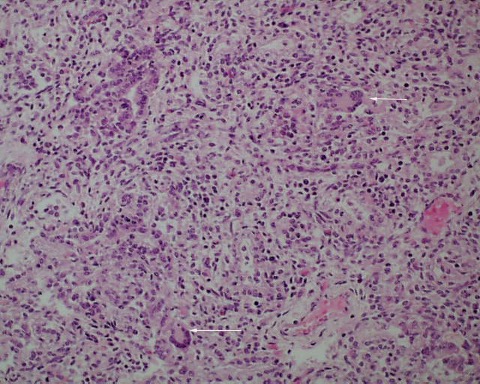

Giant cell pneumonitis and interstitial pneumonitis can also be seen in stillbirth, but these features do not indicate a specific etiology19. Fungal, viral and protozoic should be excluded (Fig 14a-c).